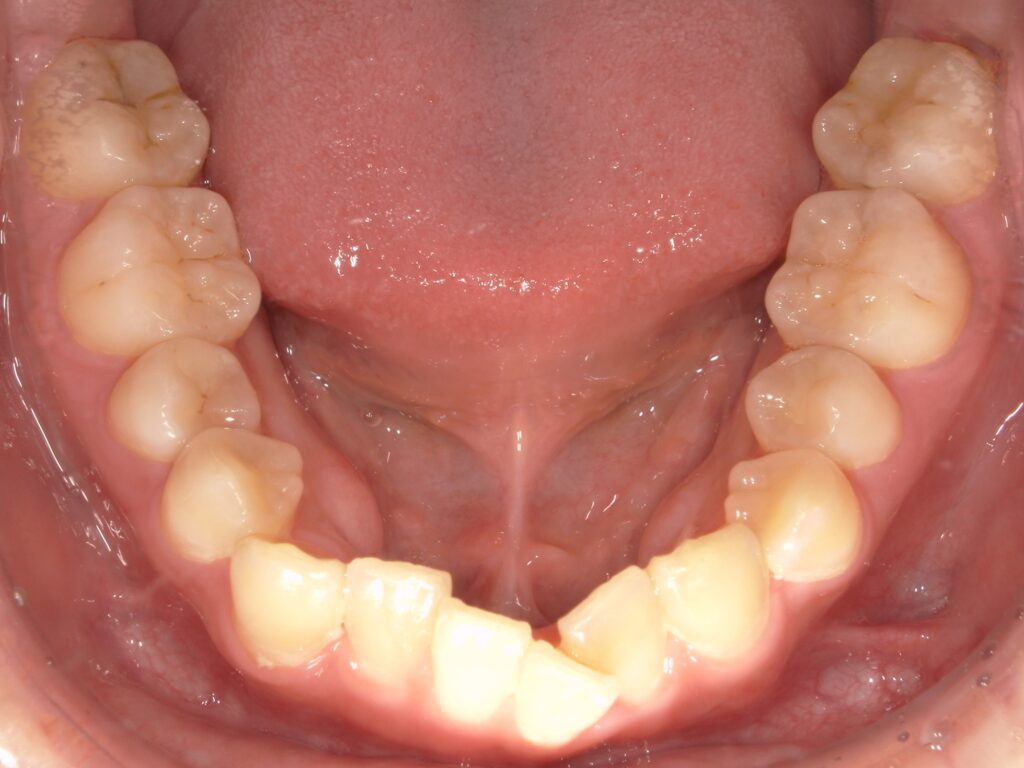

Before

After

ガタつき / 八重歯

- 30代男性

- 主訴:ガタつき

- 矯正方法:インビザラインの抜歯矯正

- 治療期間:12ヶ月

- 治療費:935,000円

- その他ご要望:お仕事柄、ワイヤーではなく目立たないマウスピース型をご希望。分割払いをご希望。

- 詳しくはこちら

ご相談内容 ガタつきが気になると30代男性からのご相談 現状と治療方針 重度のガタつきが見られます。八重歯や内側に倒れた歯があり、顎のスペースに対して歯が並ぶスペースが不足していたためインビザラインで片側の抜歯矯正を行いました。 治療結果 ガタつきを12ヶ月で改善することができました。 振り返り 今回の患者様はガタつきが重度だったため、片側の抜歯矯正を選択しました。ご本人は治療期間が2年ほどかかると思われていたようで、このガタつきが12ヶ月で改善したことに大変喜ばれていました。人前に出るお仕事柄、目立つ装置は避けたいとのご希望があり、目立たないマウスピースで改善することができました。 リスク・副作用 マウスピースの装着時間を守っていただけないと矯正治療に時間がかかり、場合によっては治療がうまく進まない可能性があります。